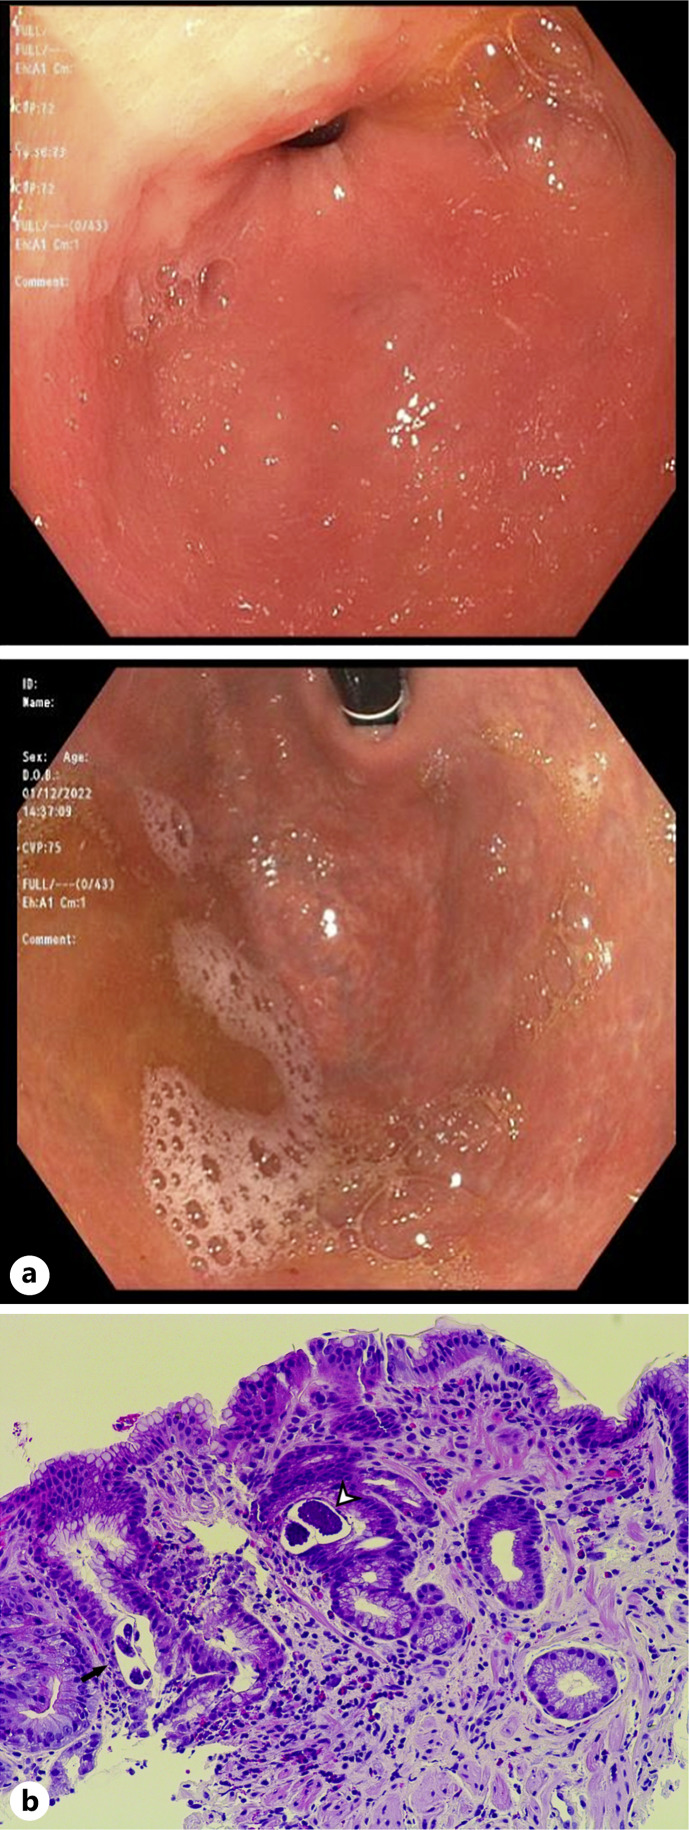

导读:蛔虫科包括至少50种肠道线虫,其中粪形蛔虫是人类中最常见的一种。由于这种寄生虫复杂的生命周期,它既可以局限于肠道,也可以传播到全身的不同器官,在免疫抑制的情况下最终导致过度感染。类圆线虫病在美国是罕见的,并伴有胃累及是罕见的。病例介绍:在这个病例报告中,我们描述了一个无症状和免疫能力的利比里亚胃十二指肠圆线虫病患者的病例,其诊断是基于内镜评估缺铁性贫血的组织学结果。结论:本病例提示在缺铁性贫血合并外周血嗜酸性粒细胞增多的高危人群中怀疑弥散性圆线虫病诊断的重要性。

Introduction: The Strongyloidae family includes at least fifty species of intestinal nematode worms, and Strongyloides stercoralis is the most prevalent one among humans. As a result of this parasite's complex lifecycle, it can either remain localized in the intestines or disseminate to different organs throughout the body, culminating in hyperinfection in case of immunosuppression. Strongyloidiasis is rarely encountered in the USA, and an associated gastric involvement is uncommon.

Case presentation: In this case report, we describe the case of an asymptomatic and immunocompetent Liberian patient with gastroduodenal strongyloidiasis whose diagnosis was based on histologic findings during endoscopic evaluation for iron deficiency anemia.